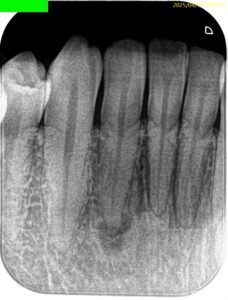

PA(2025.4.16)

Pre-op Endo Diagnosis(2025.4.16)

Pulp Dx: Normal Pulp Tissues

Periapical Dx: Symptomatic apical periodontitis

Recommended Tx: RCT